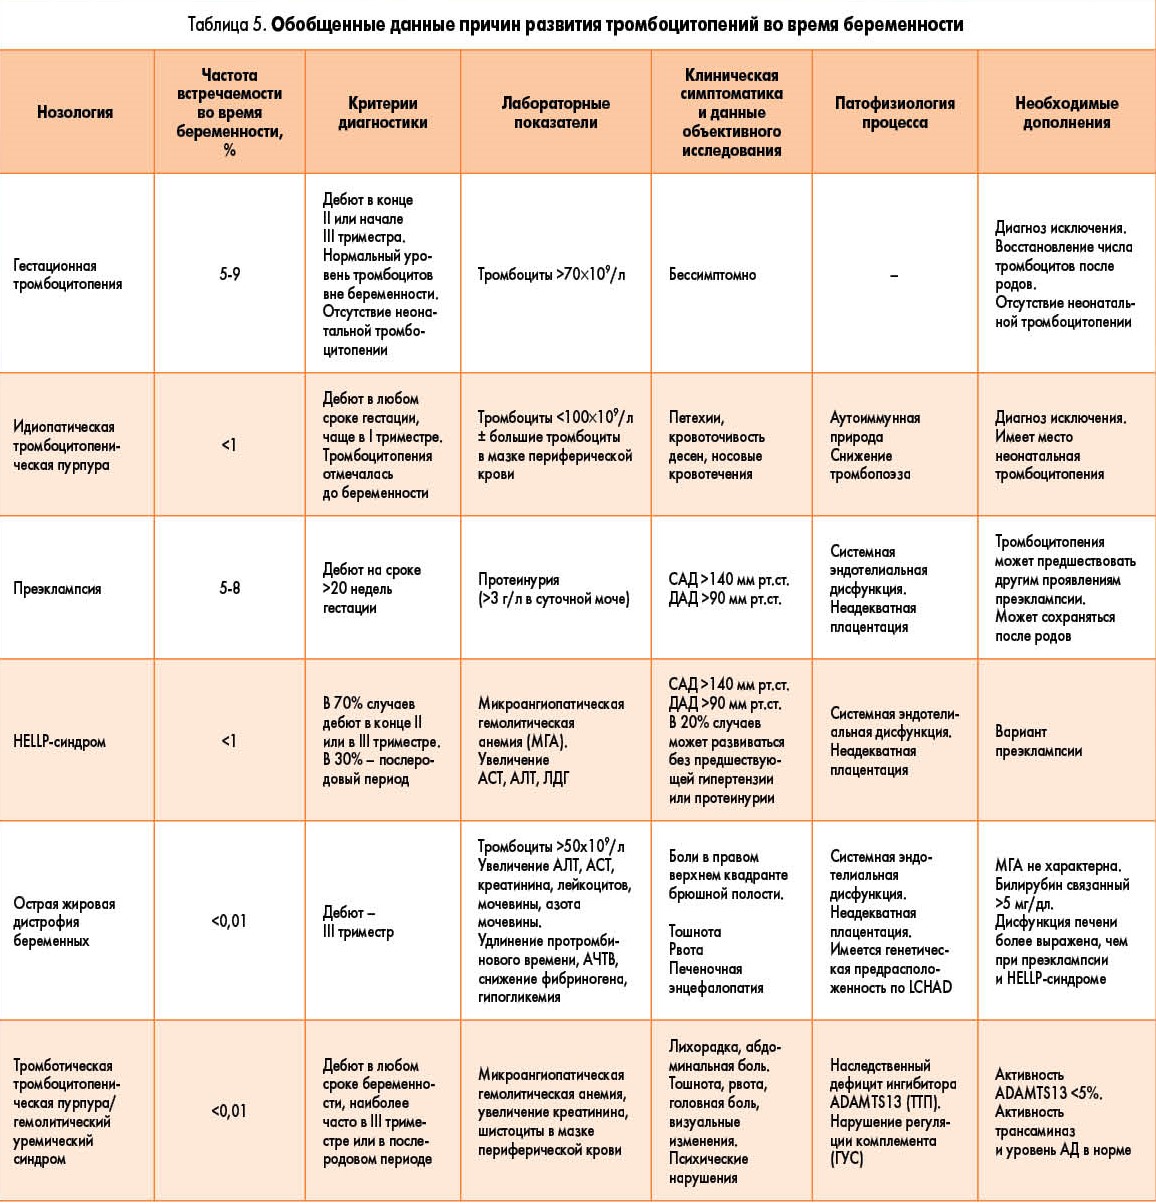

Биомеханизм родов таблица

Биомеханизм родов таблица